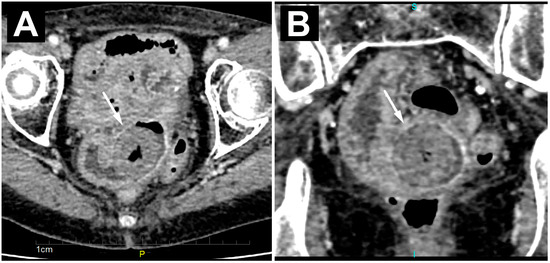

| Calcified bezoar (“Bezoar egg”) | Hyperechoic oval structure with posterior acoustic shadow within the bowel lumen | Oval, clearly demarcated mass with centrally placed gas | T1w and T2w hipointense oval mass with layered structure |